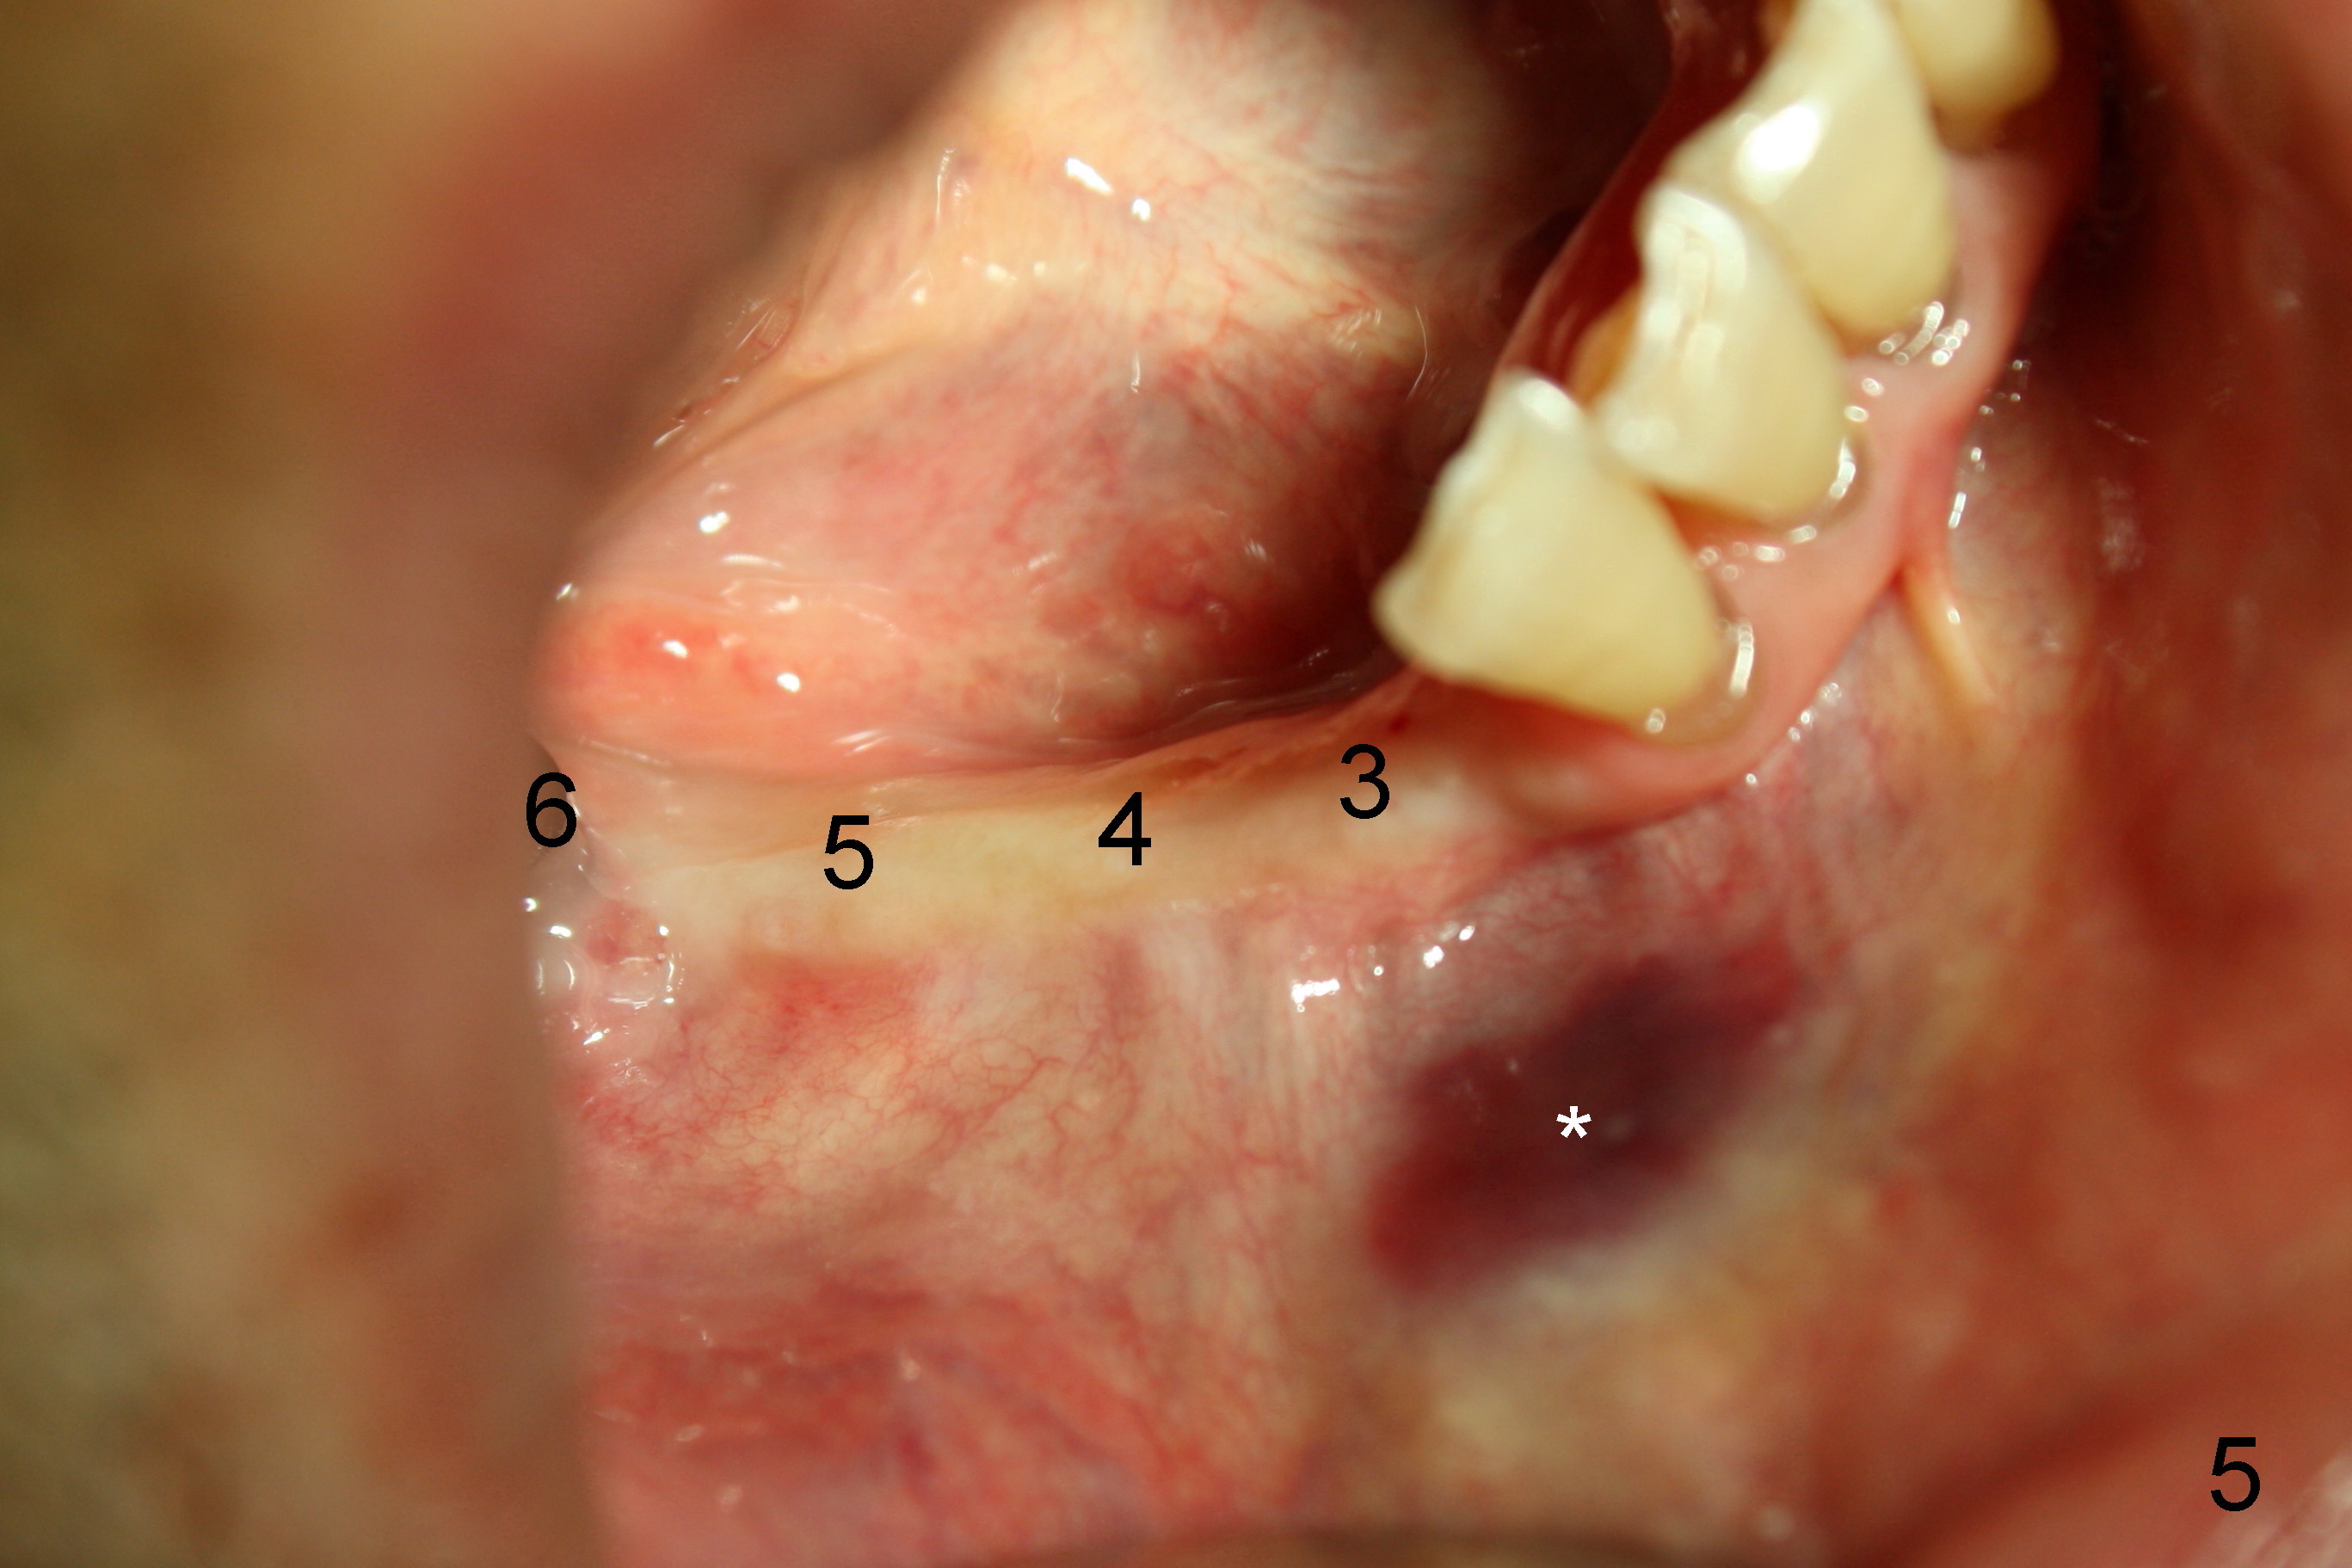

The lower right bridge (from canine (Fig.2: 3) to 1st molar (Fig.1: 6)) fails while a 77-year-old man is undergoing chemotherapy for urinary bladder cancer.  The abutments of the bridge are extracted without plan for implants (Fig.4).   Four months later, the patient returns for implants (Fig.3), but the ridge is narrow (Fig.5).  While 2 of 3x14 mm 1-piece implant are placed at the canine and 1st bicuspid sites, 2 piece ones at the 2nd bicuspid and 1st molar sites (Fig.6: 3.5x11 mm, 5x14 mm).  Soft (Fig.7-10) and hard (Fig.11) tissues heal 1 week (Fig.7) and 4 months (Fig.8-11).  There is minimal bone resorption 1 year 7 months post cementation (Fig.12,13, non-splinting).  It appears that narrow diameter implants are a valid solution to narrow ridge at the sites of the lower canine and premolar.  As long as there are enough implants for function, the crowns are not necessary to be splinted.  Surprisingly, the patient starts flossing after implant restoration.  Retrospectively an immediate provisional bridge should have been fabricated.

There appears to be no bone loss 2 years 5 months post cementation (Fig.14).  Gingival bands form around the implants at #27-29 three years 1 month post cementation (Fig.15 *).